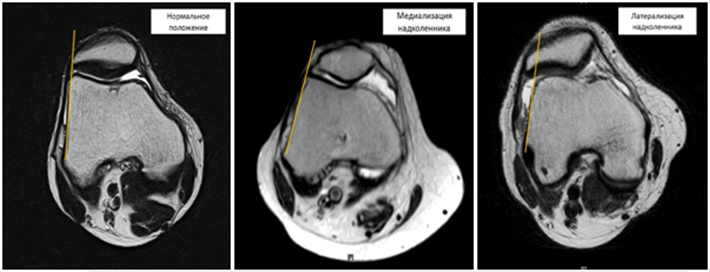

Лікування медіалізації (зміщення всередину) і латералізаціі (зміщення назовні) надколінка

Медіалізація (зміщення всередину) і латералізація (зміщення назовні) надколінка — найчастіше ускладнення дисфункції капсульно-зв'язкового апарату колінного суглоба що зустрічається. Дане захворювання супроводжується незначними болями і «хрускотом» в області колінного суглоба, які виникають при згинанні колінного суглоба і при тривалому сидінні з зігнутими в колінах ногами. Незначні, спочатку, болі з часом посилюються, набувають ниючий характер і прагнення пацієнтів сидіти з витягнутими (розігнутими в колінах) ногами. Дане захворювання призводить до розвитку артрозу надколіноково-стегнового (пателло-феморального) суглоба і значного зниження якості життя.

Дислокація (медіалізація або латералізація) надколінка можуть бути як вродженими, так і набутими. Вроджена дислокації надколінка обумовлена неправильним розвитком власної зв'язки надколінника і неправильним формуванням точки прикріплення цієї зв'язки, що призводить до порушення осі ковзання надколінка по стегновій кістці і його зміщення. Набута дислокація надколінка розвивається в результаті травм області колінного суглоба, які призводять до повного або часткового пошкодження зовнішньої або внутрішньої натягуючої зв'язки надколінника. Зазвичай пошкодження натягуючих зв'язок надколінника не діагностуються, а біль проходять через 5-7 днів після травми. Пошкоджена зв'язка зростеться з формуванням рубця, який з часом розтягується в результаті чого порушується рівнодію бічних сил, що діють на надколінок, і останній зміщується або назовні, або всередину.